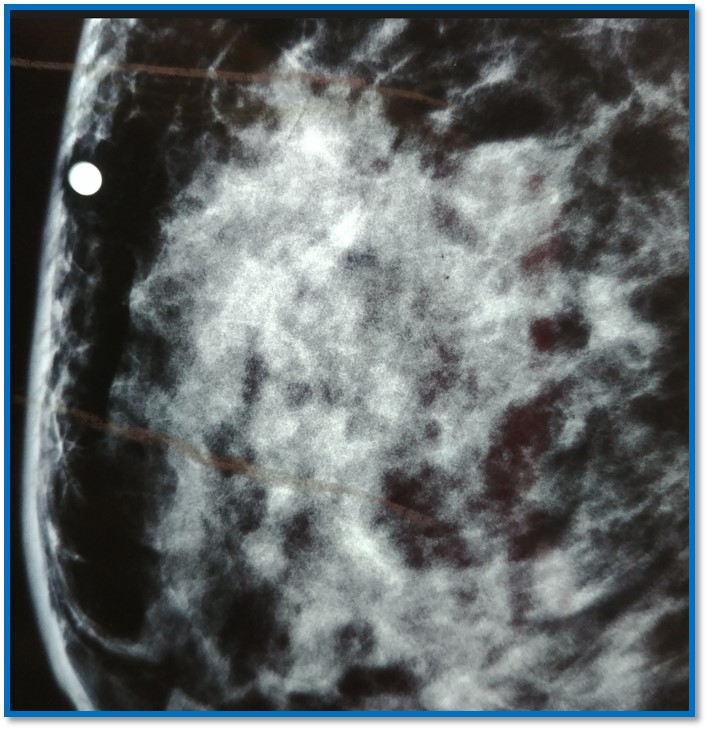

Mastografía:

Se realizó Biopsia con aguja de corte con Dx de carcinoma ductal infiltrante SBR 8 en etapa clínica IIIC recibió quimioterapia neoadyuvante. Se realizó mastectomía con linfadenectomía ipsilateral.

Imagen macroscópica del tumor residual: